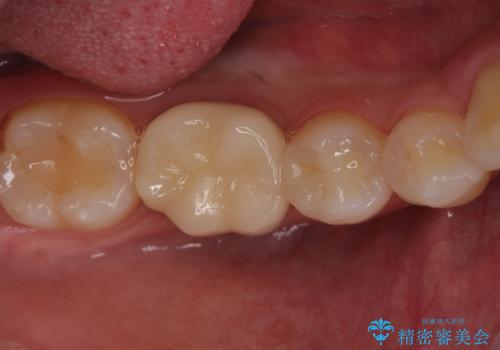

銀歯のやり替え セラミックで白い歯に

銀の詰め物を白い物にしたい